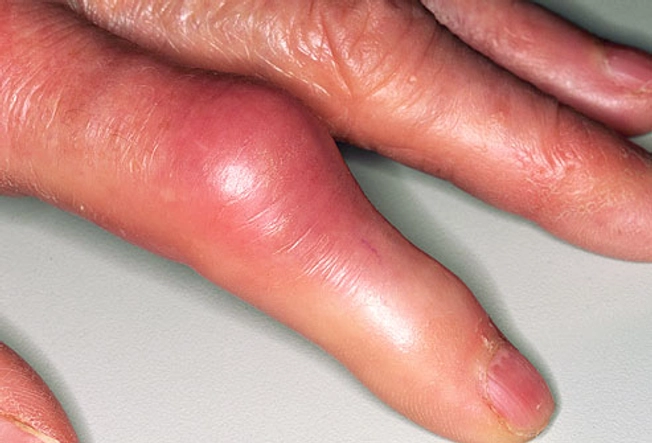

통풍의 대표적인 증상은 급격한 발작성 관절통입니다. 이러한 관절통은 대개 한쪽 발가락의 근처에 위치한 무릎, 발목, 발가락, 손목 등의 관절에서 발생하며, 강한 통증과 함께 염증이 발생하여 발적이 생길 수 있습니다. 발적은 종종 발가락을 둘러싸며 발생하며, 대개 하나 또는 두 개의 관절에서 동시에 나타납니다. 발적은 대개 몸의 상하층에 대한 분포도가 높습니다.

통풍 발작의 지속 시간은 각각 다르며, 발작이 길게 지속될수록 통증이 더욱 심해질 수 있습니다. 통풍은 발작성으로 발생하며, 증상이 발생한 부위는 화농성 관절염과 같은 감염 질환에서 나타나는 증상과 비슷하게 보입니다. 하지만, 화농성 관절염과는 달리 증상은 급격하게 시작하여 대개 1-2일 이내에 최고점에 이르고, 이후 점차적으로 회복됩니다.